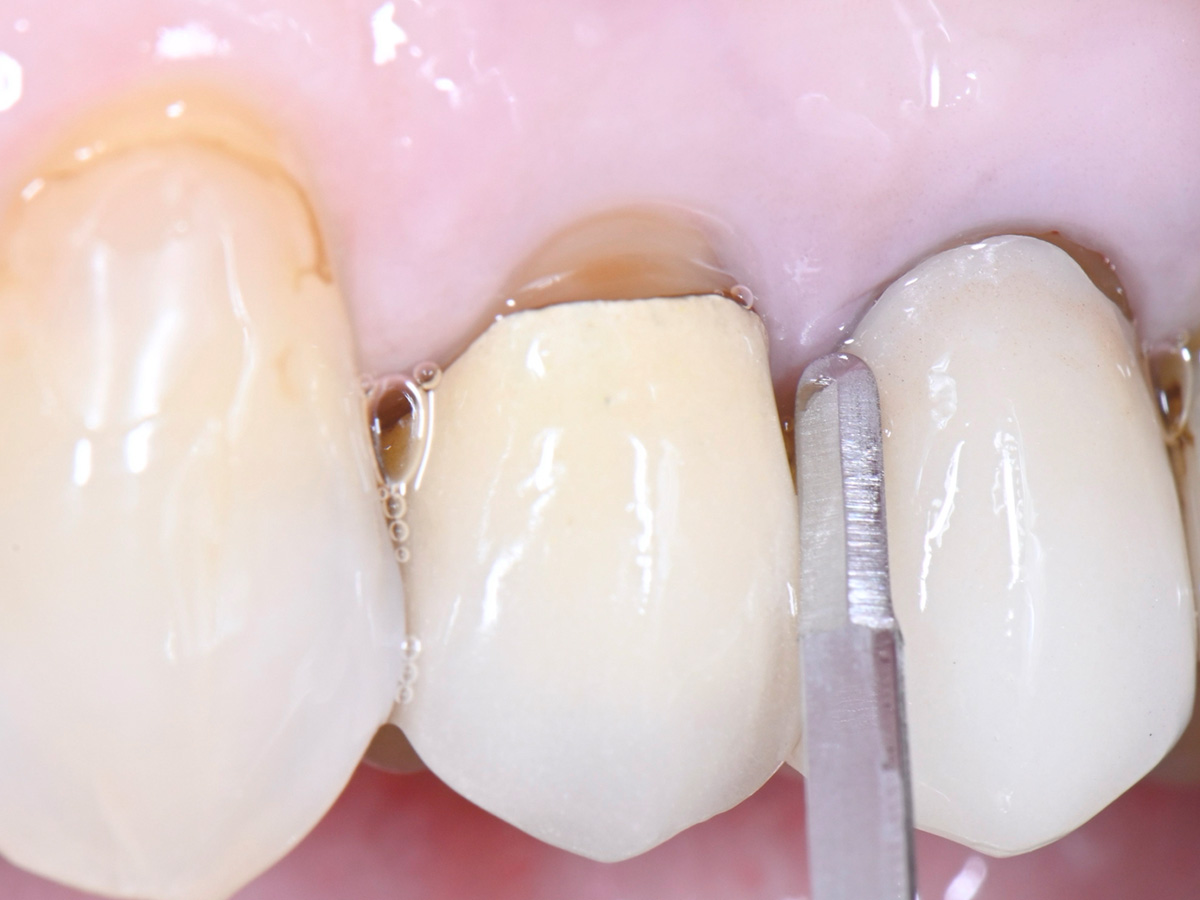

Abbildung 15

Eine individuelle Heilungskappe wird am Ende auf das Implantat aufgeschraubt

Abbildung 16

Klinisches Abschlussbild nach Einsetzen einer verschraubten Implantatkrone